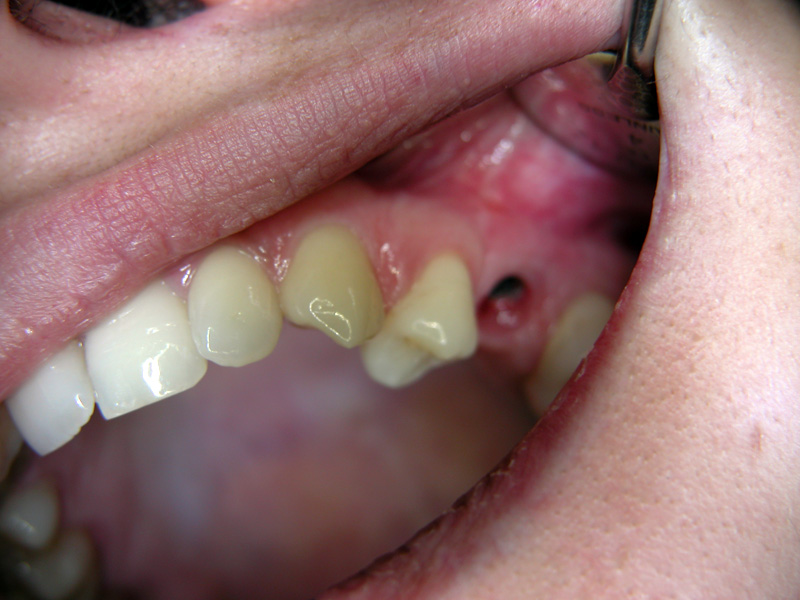

Implante - Galerie Foto

Caz I